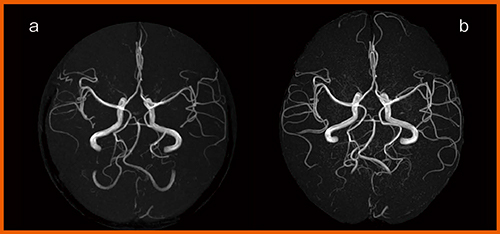

図1の頭部MRA画像では,IP-RAPID使用により,画質を維持しつつ,通常の画像(図1 b)に対し,撮像時間を55%短縮できる(図1 a)。また,IP-RAPIDのノイズ低減を空間分解能に還元すれば,同等の時間で分解能が1.2倍高い高分解能の画像が得られる(図1 c)。

図1 IP-RAPIDを使用した頭部MRA画像

bではIP-RAPIDを応用した高画質化により,空間分解能が向上している。